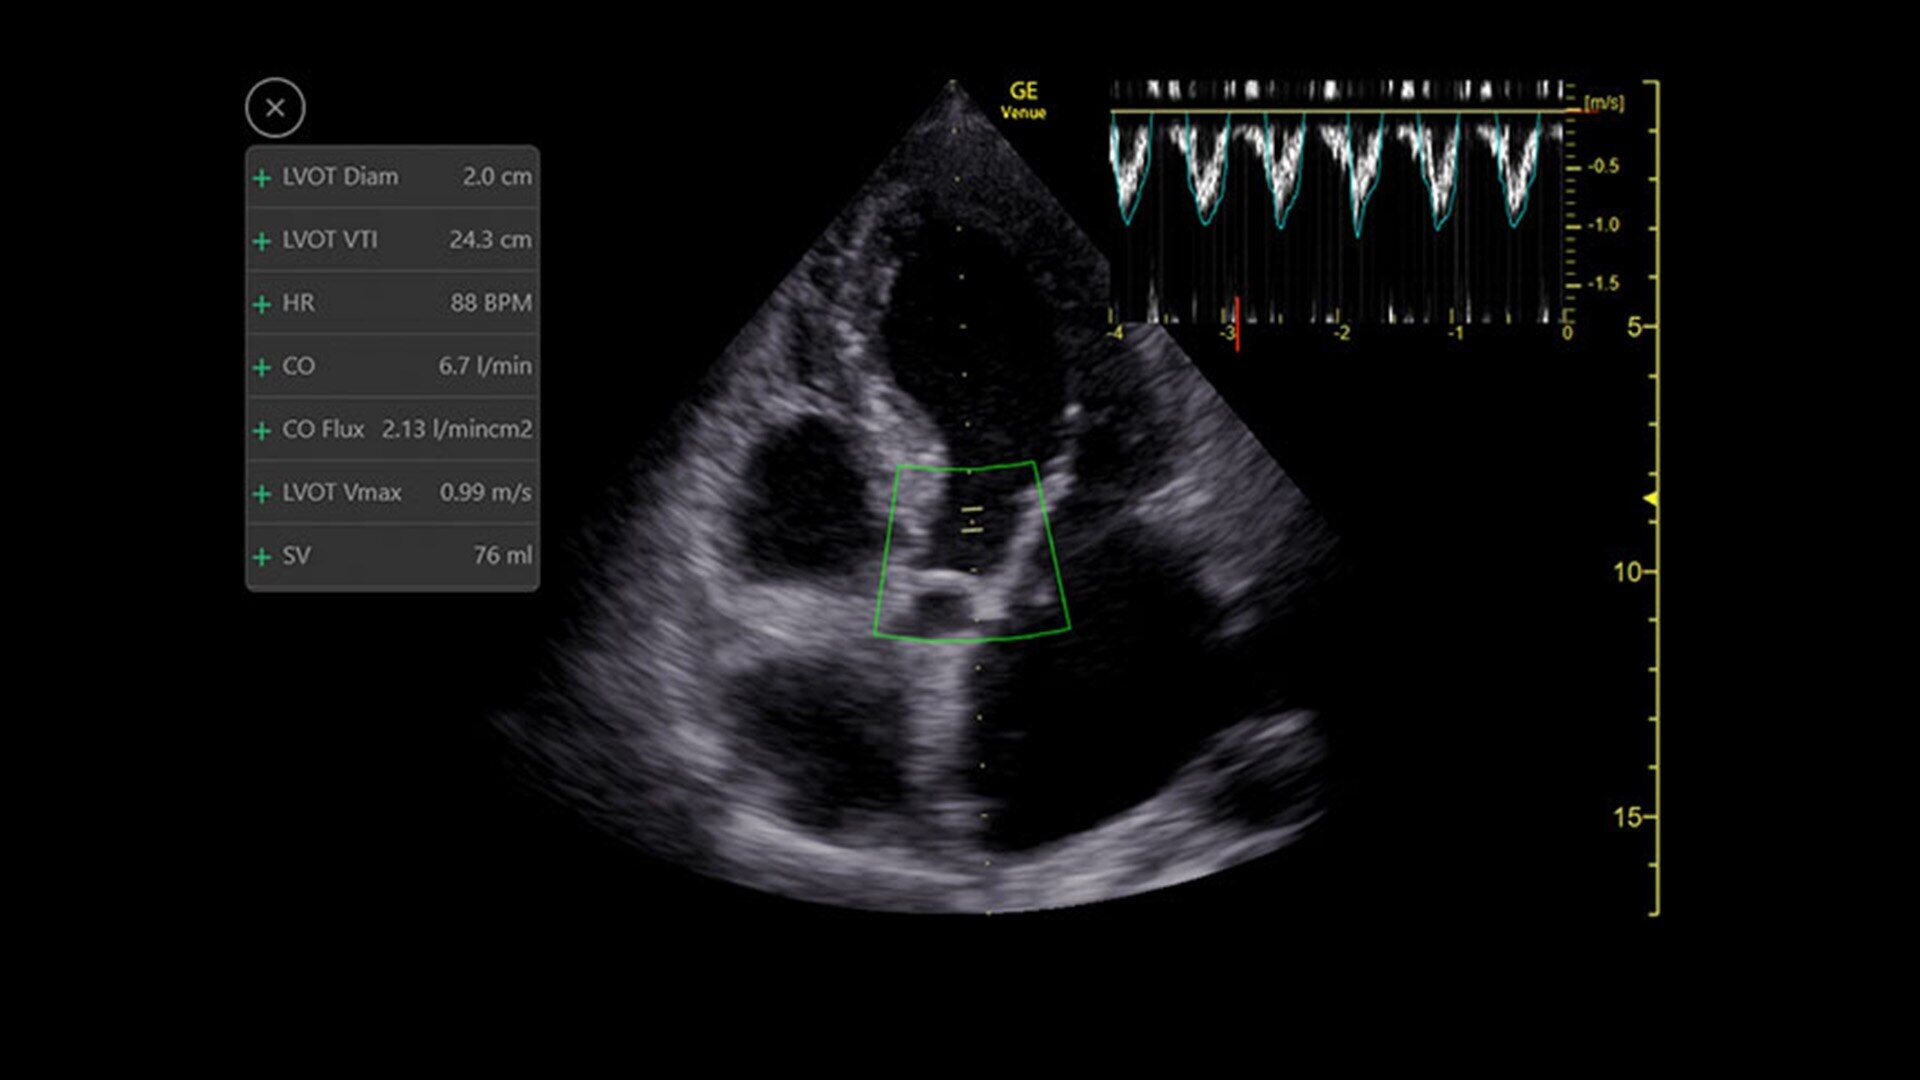

Shock Toolkit

Automated shock assessment

Medical shock in its many forms is a leading cause of death around the world.1 While ultrasound can help identify the cause of shock, it can require many manual steps and the guidelines can be complex. The Shock Toolkit quickly gets you the information you need to make fast decisions when triaging patients in shock. With tools such as Auto B-Lines, Auto VTI and Auto IVC, it simplifies a complicated process by utilizing automated calculations that focus on key indicators of patient status; the heart, lungs and inferior vena cava.

Real-Time EF

For accurate, instant, and rapidly updating results

Capture precise results instantly without requiring ECGs—thanks to Real-Time EF, an AI tool that continuously calculates real-time ejection fraction during live scanning in apical 4CH view. And for improved accuracy, its integrated quality indicator helps users select an optimal view for generating exacting results. Reducing the time it takes to reach a result while helping provide consistency, a study found that Real-Time EF results are within ±10 points of experts in 86% of cases.2